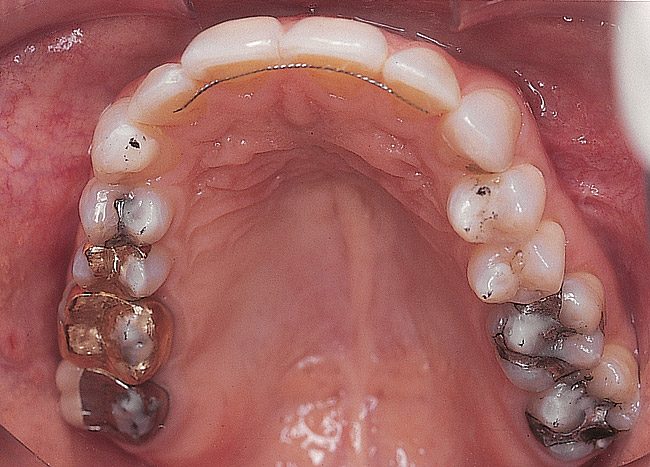

Figure 2  Preoperative maxillary occlusal view.

Figure 2